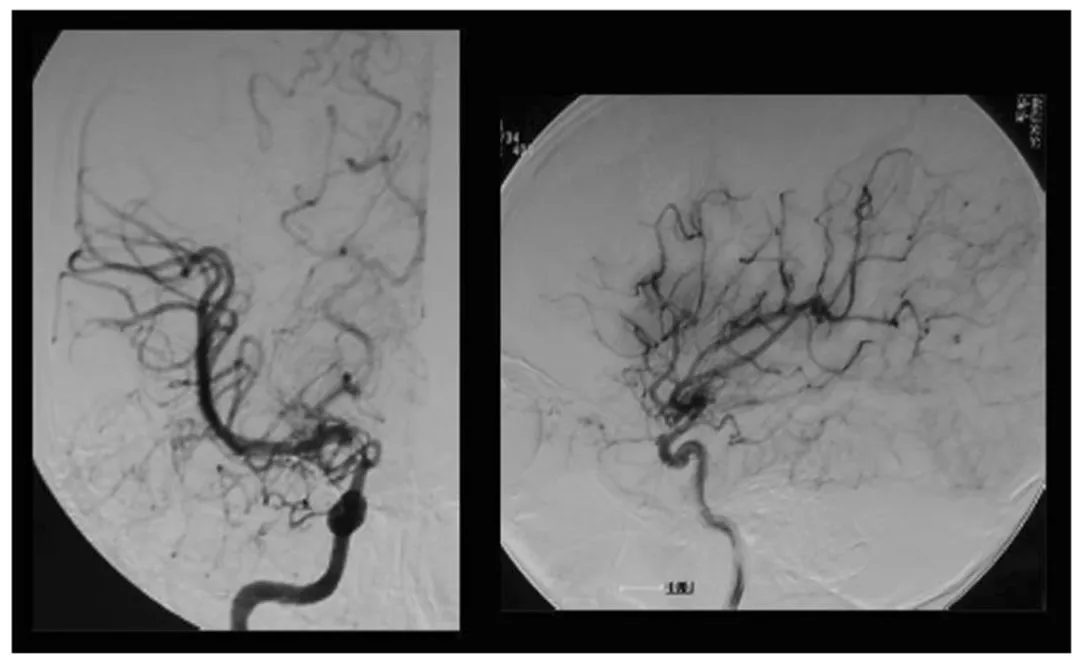

图1术前右颈动脉血管造影显示颈内动脉末端顶部烟雾血管形成,左图为前后位投照,右图为侧位投照

血管造影结果显示:右侧颈内动脉末端存在狭窄,颅内形成典型烟雾状血管,病情处于铃木分期II期(早期阶段),趋近III期进展;左侧血管目前未见异常。(图1)